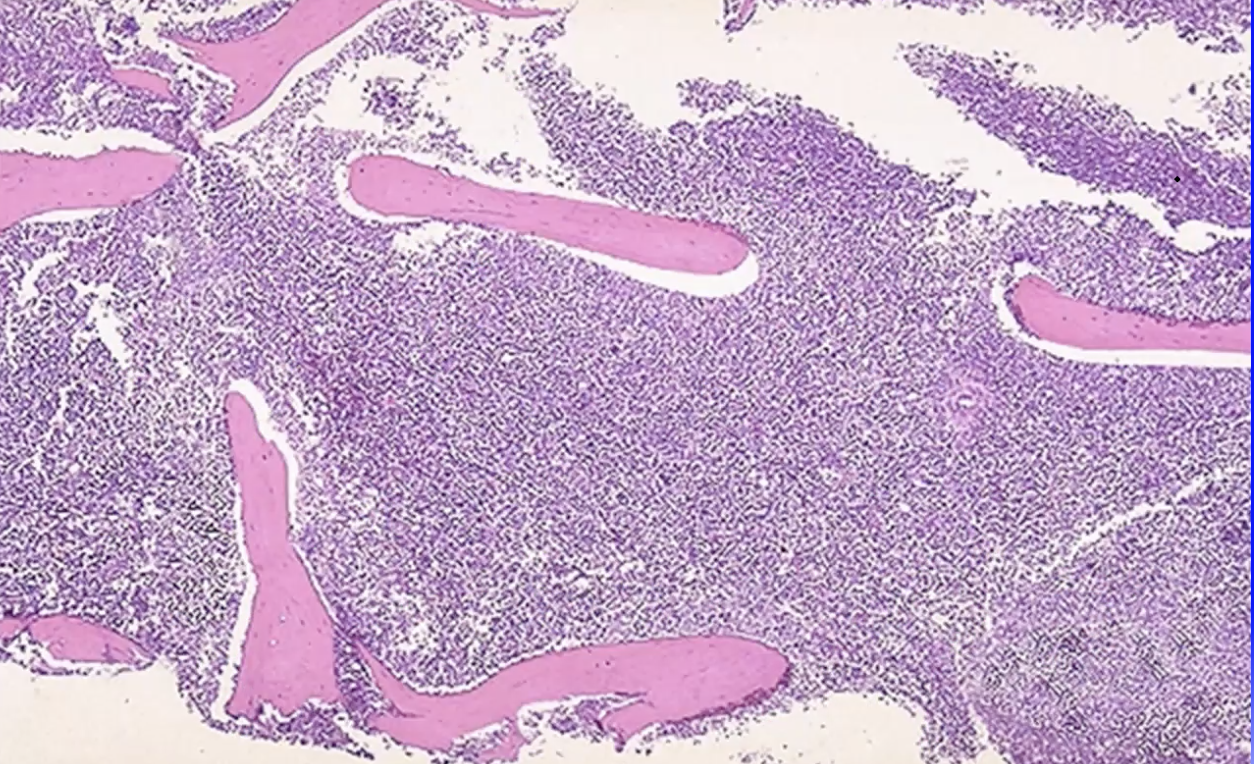

Q

A

Bone marrow bx: CLL